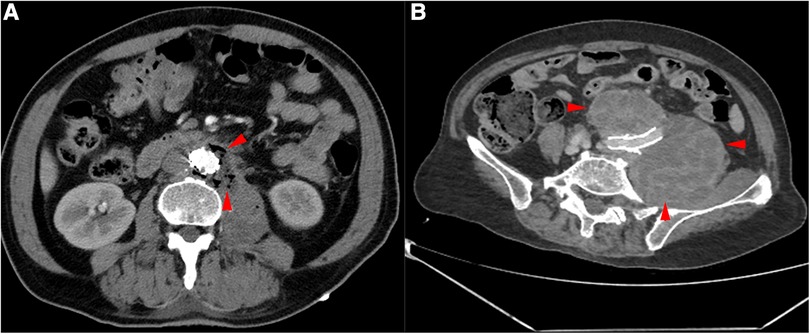

This retrospective study was approved by the Ethics Committee of Nanjing Drum Tower Hospital (registration number: 2017-015-05), and all patients provided consent for their participation. Between November 2021 and December 2022, patients with SGI were treated with removal of the infected grafts and surrounding infected tissues and revascularization (five men, one woman; mean age, 64 years; range, 49–79 years). Prior to identification of the specific infection and sensitive antibiotics, patients were treated with empiric broad-spectrum antibiotics, and surgical treatment was performed when the patient's clinical symptoms were relieved (abdominal pain, elevated body temperature and presence of inflammatory indicators). If the patient's condition worsened, emergency surgery was considered. All patients presented with postoperative fever or pain after EVAR (persistent fever in five patients and pain in the left lower abdomen in one patient). Currently, the diagnosis of SGI relies mainly on imaging, clinical presentation and laboratory indicators. The patients commonly presented with postoperative fever, and the imaging results typically showed an annular low-density shadow around the aorta, gas, and multiple floc shadows and lymph node shadows (with partial enlargement) (Figure 1A,B); the relevant inflammatory indicators (leukocytes, neutrophils, interleukin-6) were significantly increased. Aortic CT angiography (CTA) was commonly used, as was positron emission tomography/computed tomography (PET-CT). For some more insidious lesions, PET-CT has obvious advantages. PET-CT perfectly integrates PET and CT. PET provides detailed functional and metabolic molecular information of the lesion, while CT provides precise anatomical location of the lesion. Thus, PET-CT can achieve early detection of lesions and diagnosis of diseases (the radionuclide we used was 18F-FDG) (Figure 2A,B). Fever was defined as an axillary temperature above 38.0°C. The patient characteristics are summarized in the Table.

Figure 1

CTA of the patient's aorta. (A) Red arrows indicate the presence of gas around the aorta. (B) Red arrows indicate haematoma around the common iliac artery.